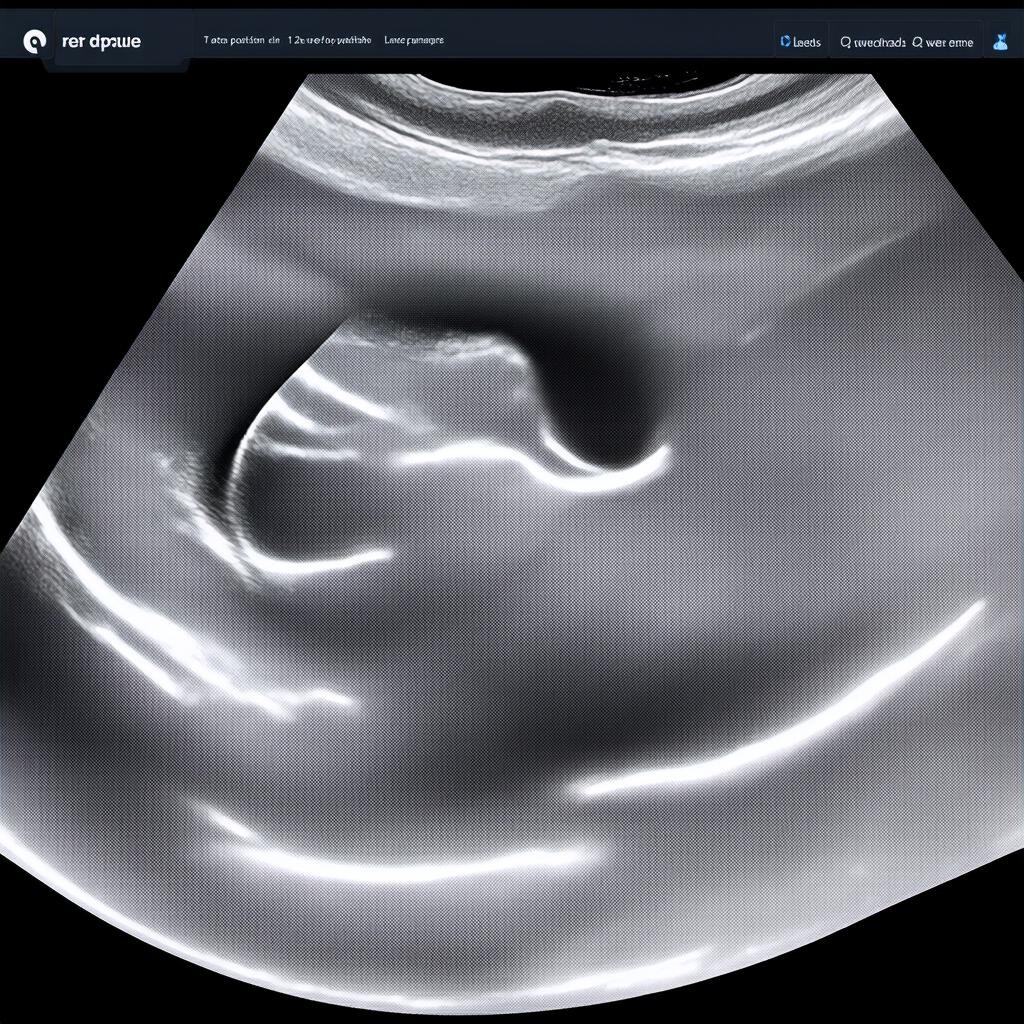

УЗИ на 12 неделе беременности — это важный этап пренатальной диагностики. В этот период врач оценивает ключевые параметры развития плода, которые помогают исключить возможные патологии. Это исследование является частью первого скрининга и включает не только ультразвуковую диагностику, но и биохимический анализ крови.

Во время УЗИ специалист обращает внимание на следующие показатели:

• КТР (копчико-теменной размер) — длина плода от темени до копчика. Норма: 45-85 мм.

• ТВП (толщина воротникового пространства) — важный маркер хромосомных аномалий. Норма: до 2,5 мм.

• Носовая кость — её отсутствие или гипоплазия может указывать на синдром Дауна.

• Сердцебиение плода — норма: 150-170 ударов в минуту.

• Структура головного мозга — проверяется симметричность полушарий.